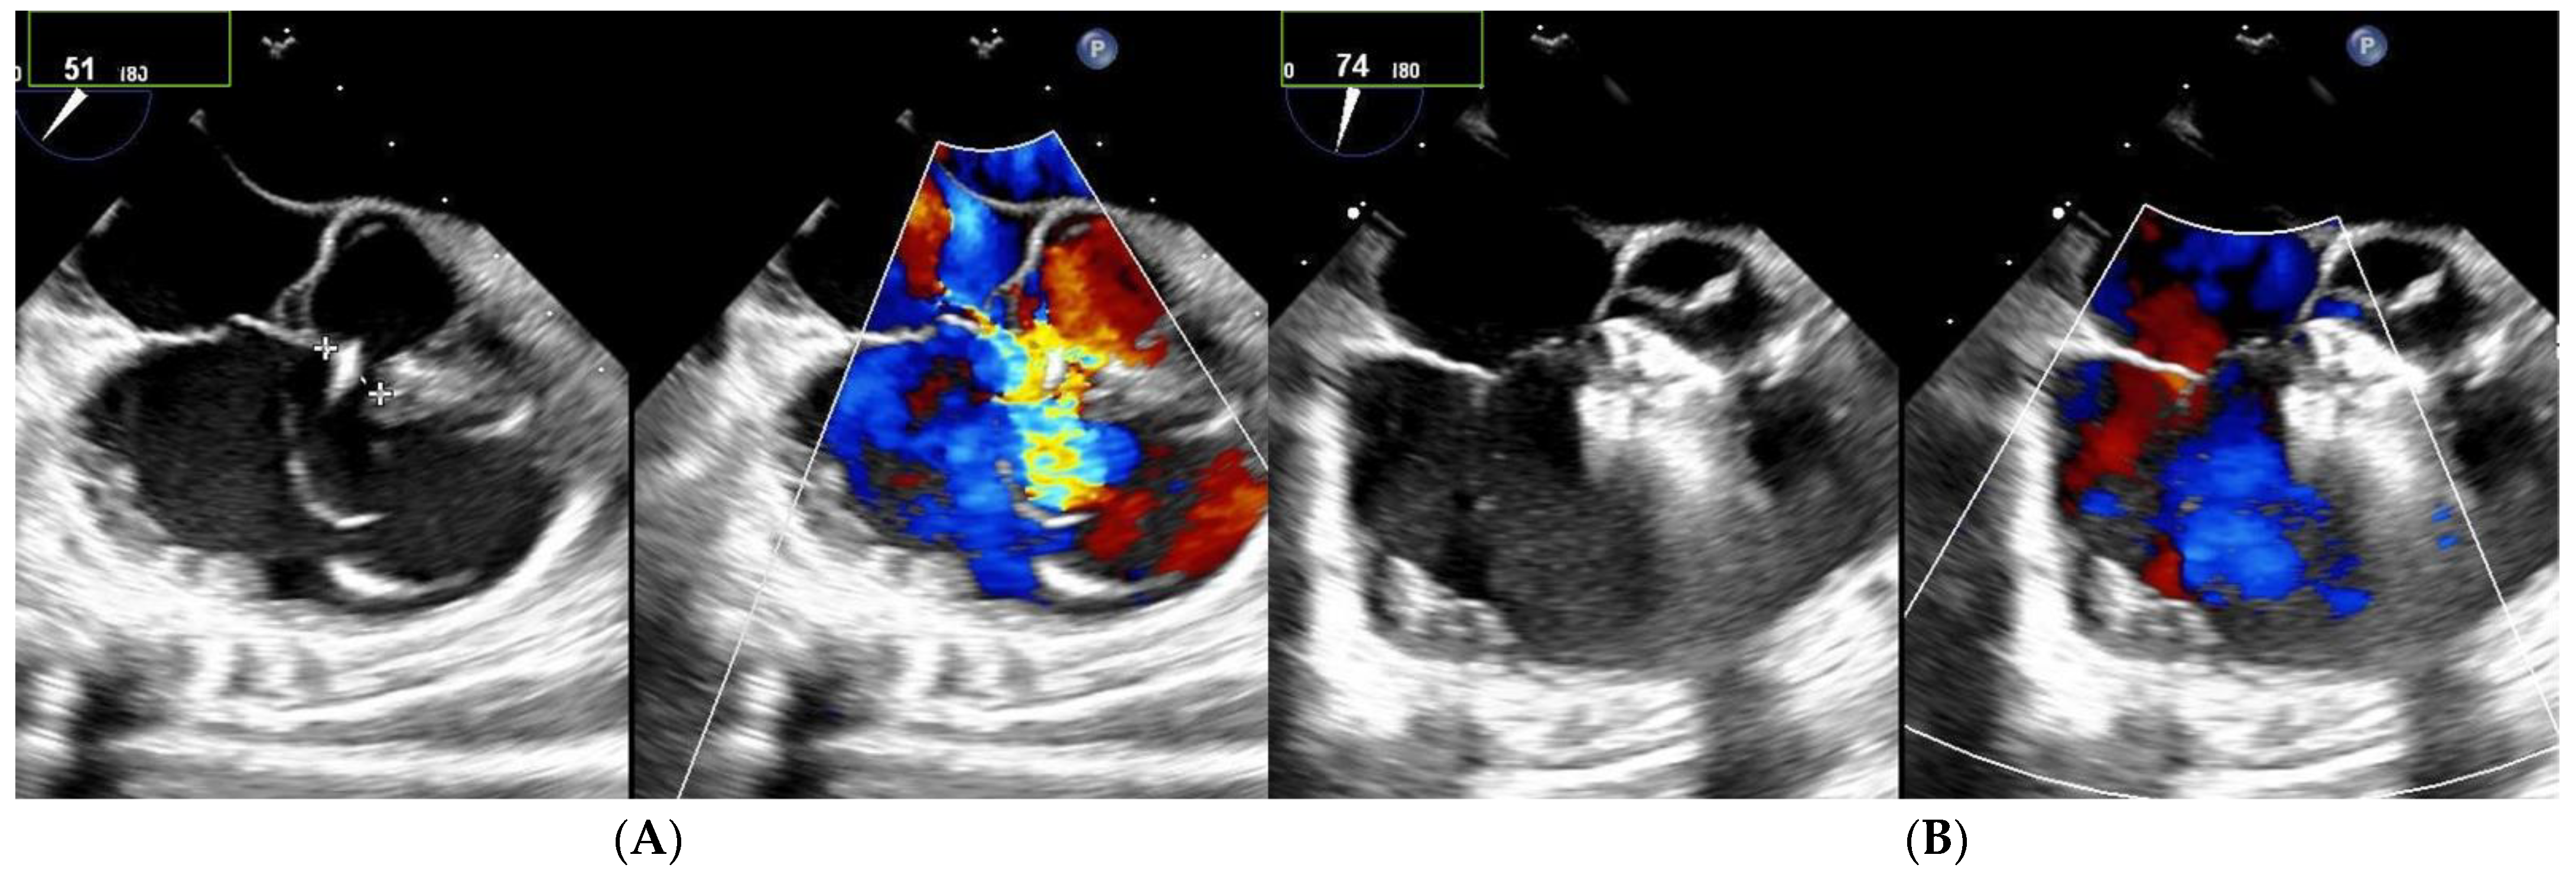

Among the 13 patients with multiple right-sided exits, 7 had no shunt during follow-up (Figure 2 and Figure 3). Among the five patients with both multifenestrated defects and Gerbode-type VSD, three achieved complete occlusion and the other two had tiny residual shunts. All the residual shunts were trivial shunts persistent at 1 and 6 months of follow-up.

Figure 2. Patient with multifenestrated PmVSD. (A) Left: transesophageal echocardiography, notice the 2 jets to the RV. (B) After closure with MFO 14/12 mm device, no shunt is observed on color Doppler echocardiography.